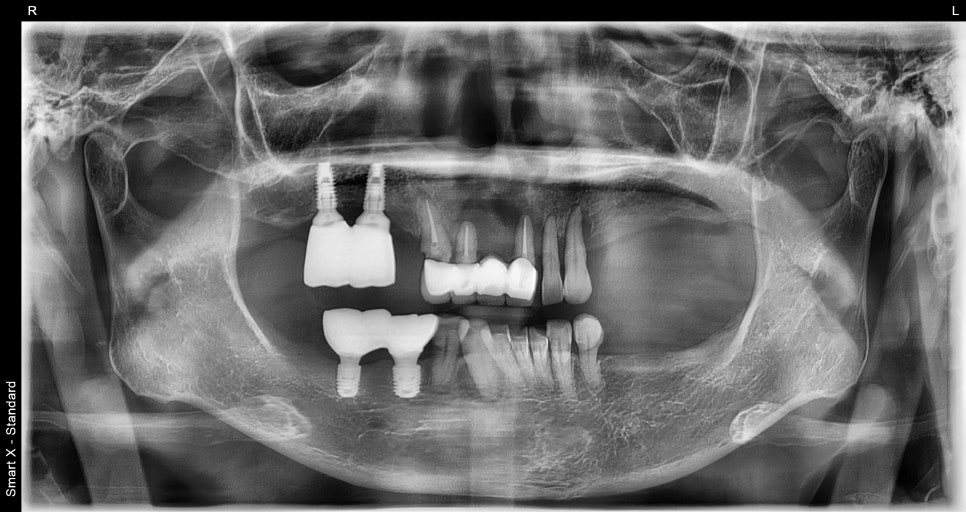

처음 내원하셨을 때의 상태

전체임플란트 전

환자분은 앞니·어금니 여러 부위가 약해져 있었고,

남아 있는 치아 또한 흔들리거나 깨져

기능을 거의 하지 못했습니다.

특히 어금니가 이미 빠져 있는 부위가 많아서

부드러운 음식 외에는 섭취가 어려운 상태였습니다.

정밀 검사를 진행해보니

전체적인 치주 구조가 많이 무너져 있어

부분 치료로는 회복이 어려운 상황이었습니다.

CT 기반 진단으로 세밀하게 분석

서울오브치과병원에서는

3D CT와 구강스캐너를 통해

뼈의 두께, 흡수 정도, 신경 위치, 잇몸 높이,

교합까지 모두 분석합니다.

검사 결과, 상악과 하악 여러 부위에서

뼈가 많이 흡수된 상태였고,

임플란트를 심기 위해서는

여러 부위에서 뼈이식(GBR)이 반드시 필요했습니다.